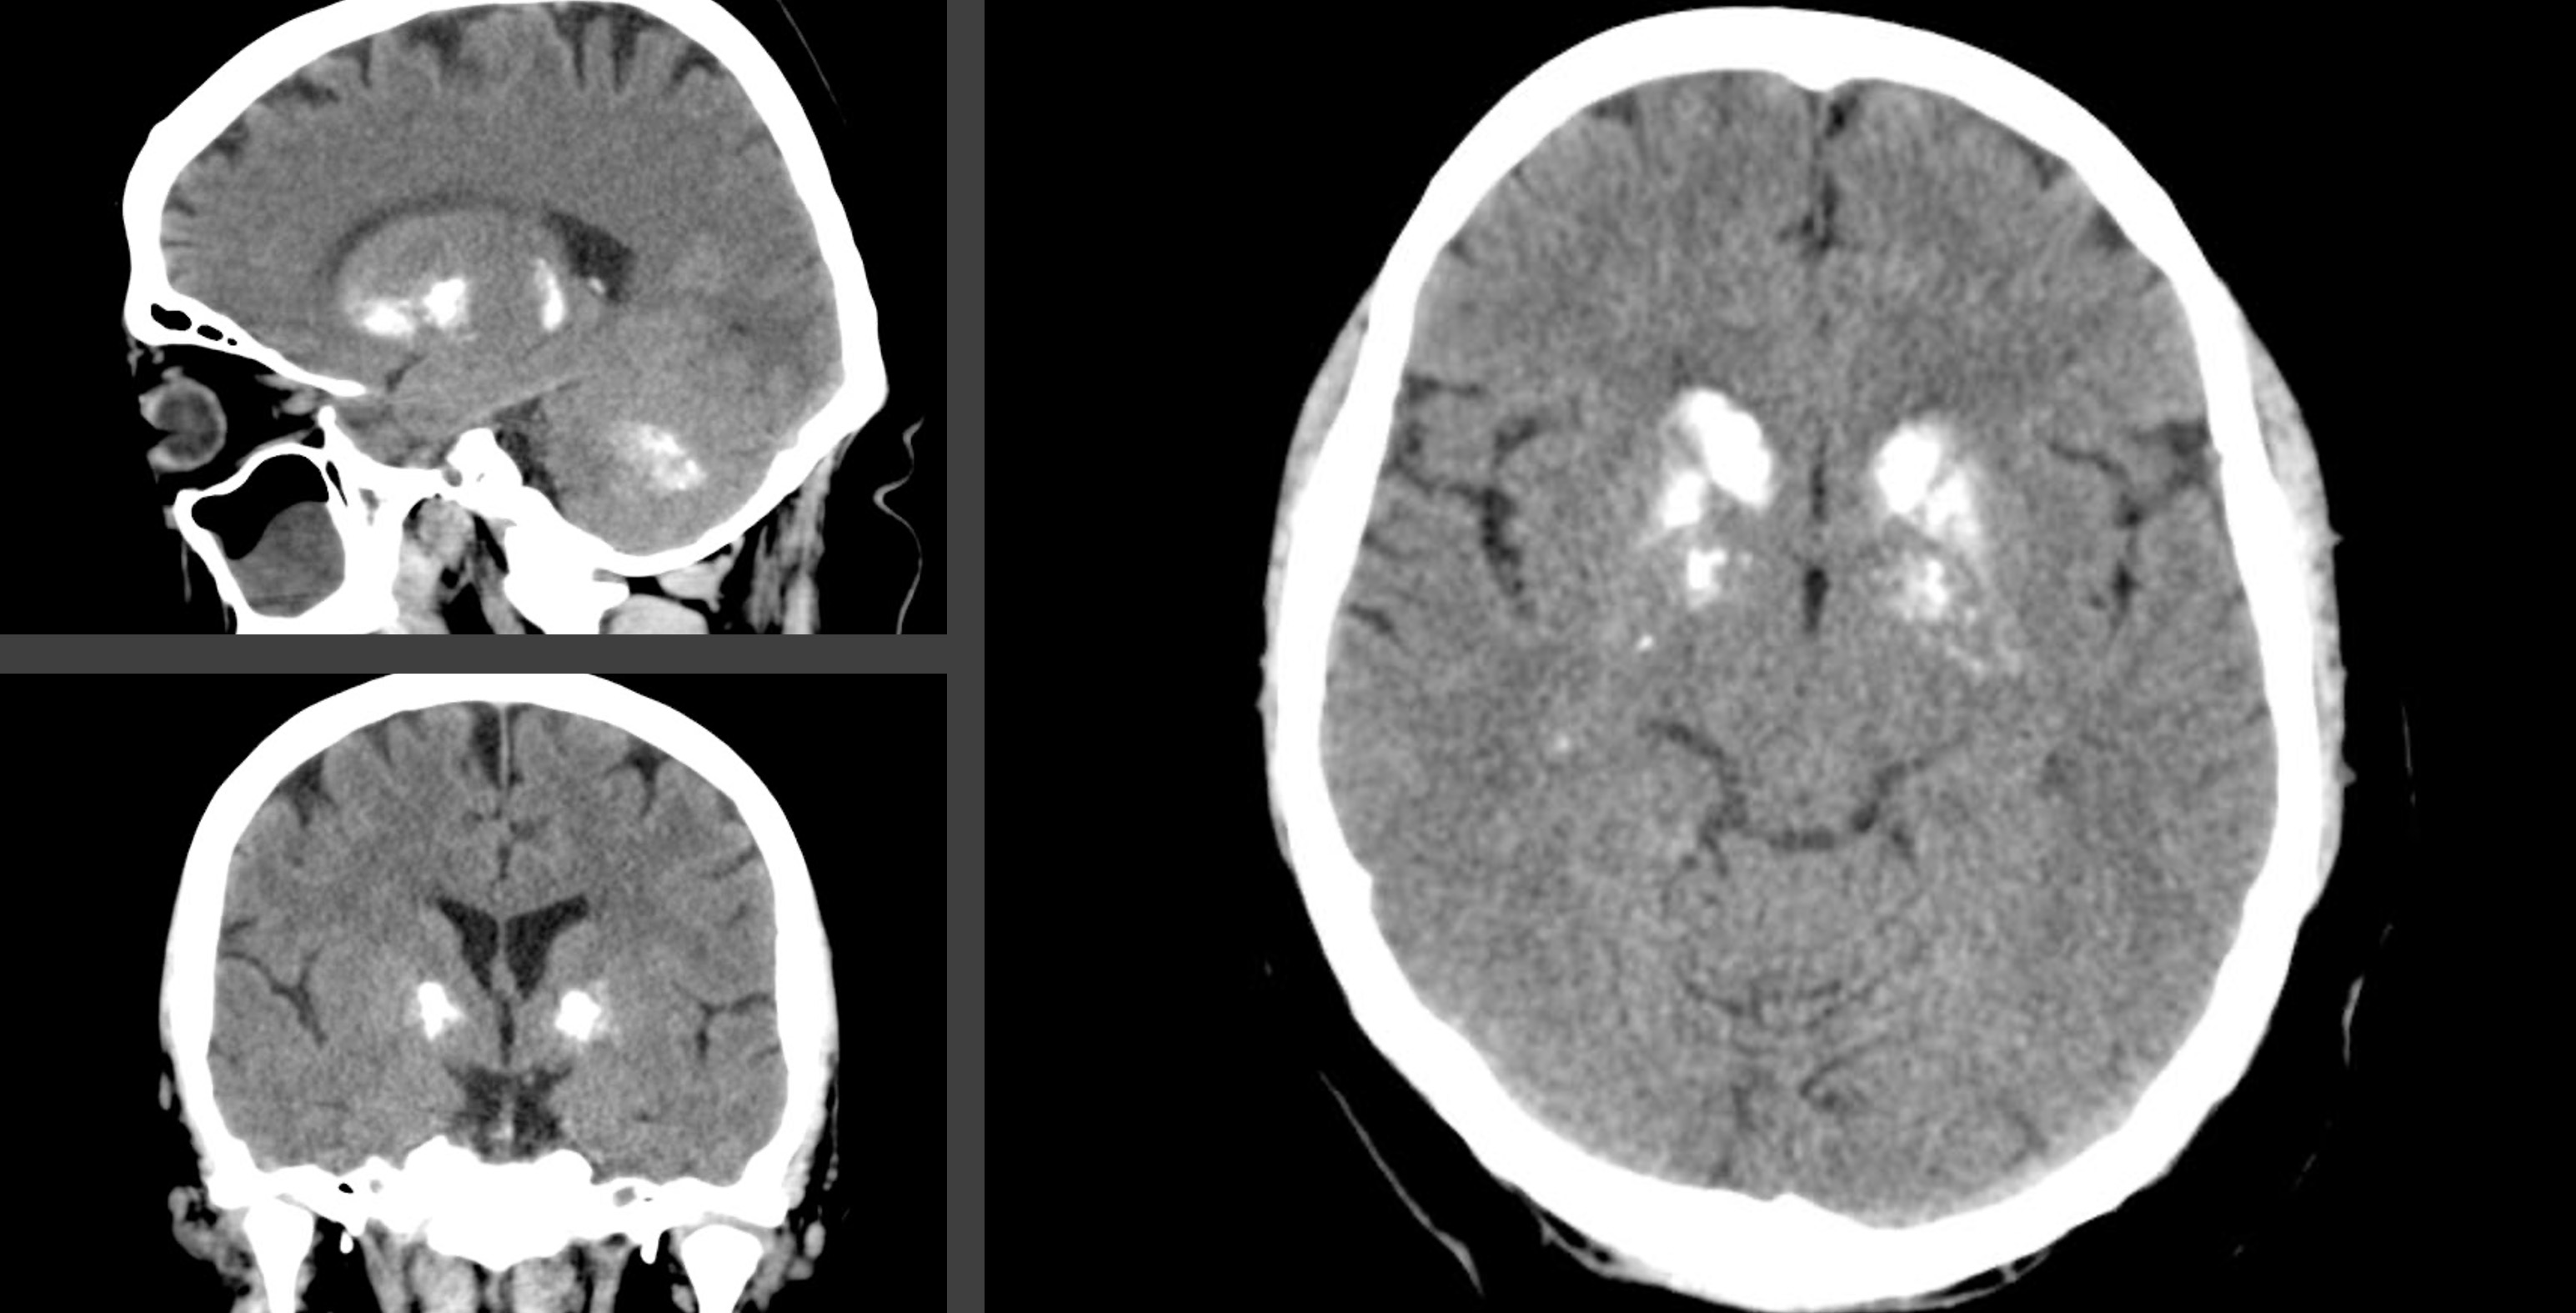

Fahrs sykdom er en genetisk tilstand kjennetegnet av dystoni, ataksi, parkinsonisme og ulike nevropsykiatriske symptomer som følge av symmetriske forkalkninger i hjernen (figur 1). Symptomer og kliniske funn kan variere fra det minimale til det livstruende (1). Det finnes per i dag ingen effektiv behandling for denne progressive sykdommen, men den nyeste forskningen viser flere medikamentelle muligheter (2). Noen studier tyder også på at tilstanden kan være mer utbredt enn tidligere antatt (3, 4). Dette aktualiserer noen refleksjoner rundt hva sykdommen bør kalles på norsk.

Fahrs sykdom har vært mye omtalt som idiopathic basal ganglia calcification, dvs. basalganglieforkalkninger uten kjent årsak. Denne betegnelsen gir en god beskrivelse av den anatomiske lokalisasjonen av forkalkningene, men ordet idiopatisk er ikke lenger dekkende, ettersom tilstanden nå er vist å ha en genetisk årsak. Dessuten kan forkalkningene også forekomme i andre områder av hjernen, slik som subkortikal hvit substans, talamus og lillehjernen (8).

De senere årene synes betegnelsen primary familial brain calcification (på norsk primær familiær hjerneforkalkning) å være mest brukt i internasjonal faglitteratur. En fordel med denne betegnelsen er at den tydelig refererer til hjerneforkalkninger av genetisk opprinnelse. En ulempe er at betegnelsen ekskluderer tilfeller som har oppstått av spontane mutasjoner. Slike tilfeller kan omtales som primær bilateral hjerneforkalkning (5).